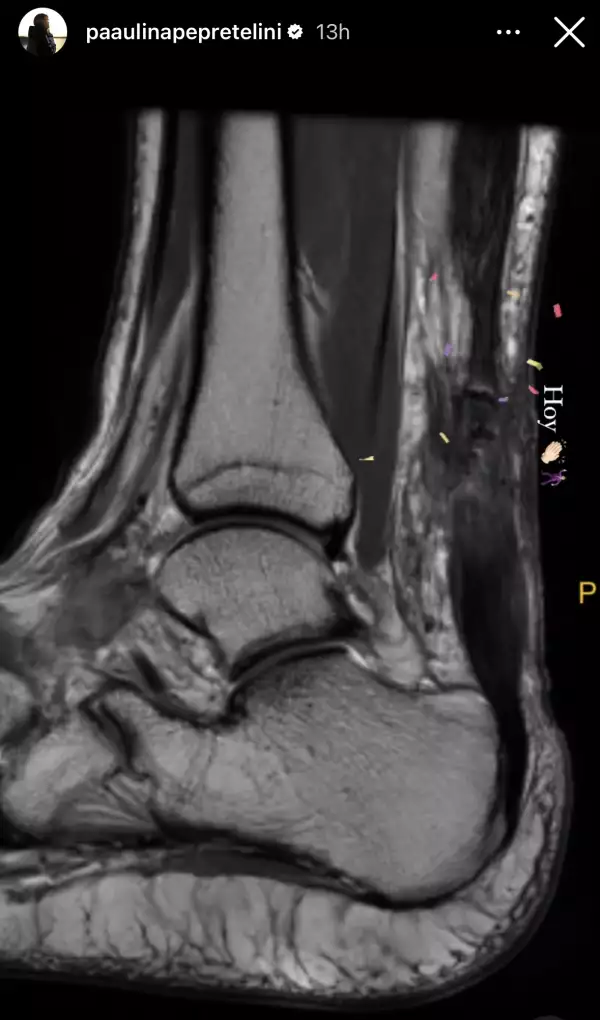

Ahora, dos meses después, parece ser que su recuperación continúa en evolución y su ánimo también. Paulina Peña está contenta porque a través de sus stories mostró como hace 12 semanas se veía la radiografía de su tobillo izquierdo y hoy parece ser que ya se encuentra mejor, incluso hasta podría bailar. Se entiende así por el emoji de aplauso que puso y al lado uno de bailarín.